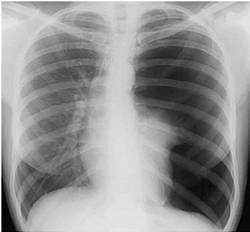

Науқас 32 жаста, кеуде жасушасы сол бөлігіндегі ауырсынуға шағымданды, дем алу қиындығымен демікпе көрсетілген. Кенеттен ауырған, жөтелдін әсерінен кеуде жасушасының сол жақ бөлігінде ауырсыну пайда болды, тездетіп демікпе үдей бастады. Объективті: ерін цианозы, кеуде жасушасының сол жақ жартысы үлкейгені соншама, тыныс алу актісінен қалып қояды, мойын тамырларының ісінуі белгіленді. Перкуссияда: сол жақта дыбыстын тимпаникалық түрі, перкуторлы сол жақ өкпенің төменгі шегі төмен түскен (аурудын ауыр жағдайына байланысты төменгі шетінің қозғалғыштығы анықталмаған). Аускультацияда везикулярлық тыныс алу кенеттен босаңсыңғаны байқалады. Кеуде қуысы шолымды рентгенографиясы таѓайындалды.

Нақты клиникорентгенологиялық сурет қандай патологияѓа үзінді:

A) Пневмоторакс

{Дұрыс жауабы} = A